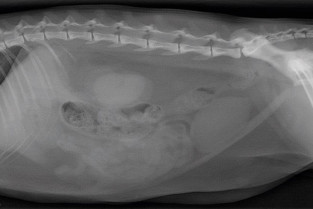

Le GEIM vous propose une séance de travaux pratiques de radiographies sur l'abdomen. Tous les aspects sont abordés sous la forme de TP de lecture de radiographies numériques sur station de travail Osirix sur Mac (3 vétérinaires maximum/ordinateur).

- adopter une méthodologie pour interpréter des radiographies abdominales chez les carnivores domestiques

- décrire la radioanatomie de l’abdomen chez les Carnivores domestiques